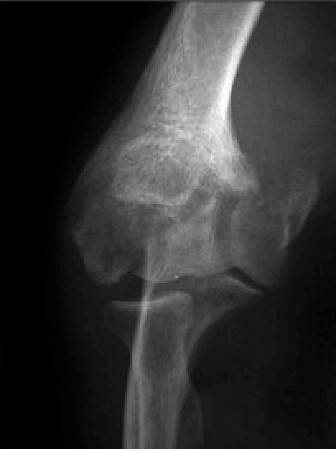

Examination reveals deformity about the elbow with no open lesions or skin tenting. He has a palpable radial and ulnar pulse and is neurologically intact. His images are shown (Figs. 2–85 to 2–88).

Figure 2–85

Figure 2–86

Discussion

The correct answer is (B). This is the most common type of elbow dislocation, and often does not cause any osseous injury. Posterolateral and posteromedial dislocation account for approximately 90% of dislocations. Adequate pre- and postreduction films are necessary to evaluate for fracture, which would change the classification to a complex injury.